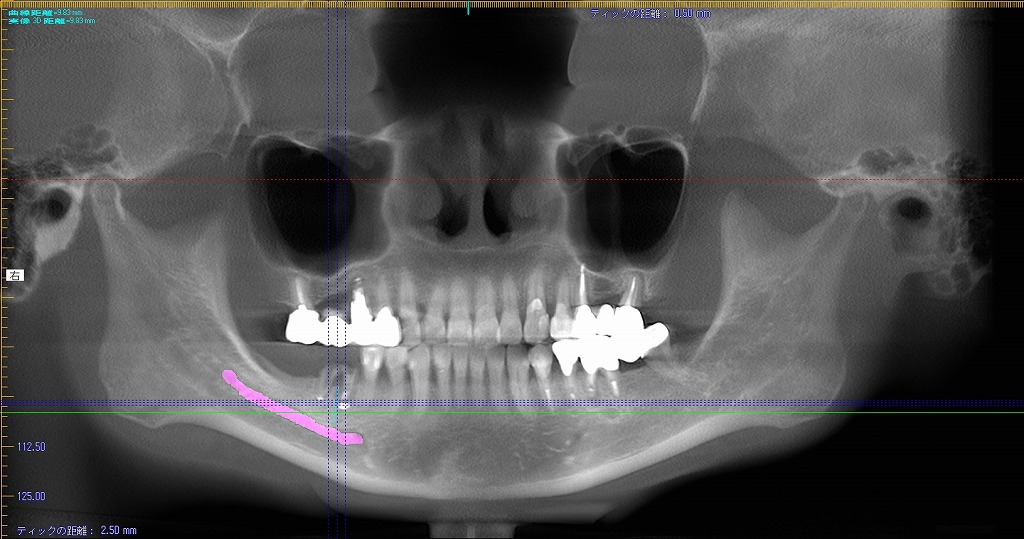

埋入時のctのパノラマレントゲンになります

埋入後を見ていただくと距離もないことがわかります

10mmのインプラントでもギリギリのところかと思います

埋入前と後のセファロ像になります